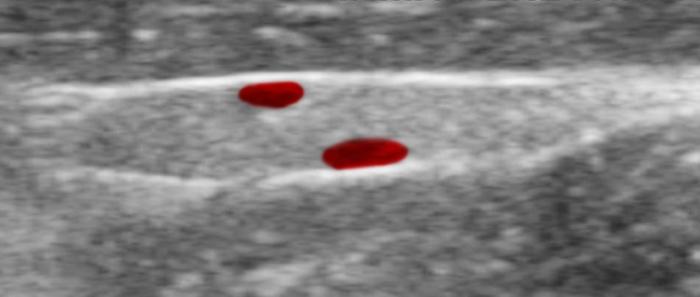

Relación entre el diámetro tiroideo (TD) y el diámetro de la arteria carótida común (CCA)

El uso de estructuras vasculares adyacentes como referencias anatómicas ha sido una estrategia útil en ecografía veterinaria para estandarizar las mediciones de órganos pequeños como la glándula tiroides. En este contexto, Bandula Kumara et al. (2019) propusieron la medición de la relación entre el diámetro tiroideo (TD) y el diámetro de la arteria carótida común (CCA) como una forma práctica de evaluar el tamaño de la glándula en perros clínicamente normales (Figura 5A-B).

Los autores realizaron un estudio en el que midieron el diámetro anteroposterior de los lóbulos tiroideos y el diámetro externo de la CCA en cortes transversales obtenidos a nivel del cuello medio. Encontraron que esta relación se mantiene relativamente constante entre razas y tamaños corporales, sugiriendo que puede ser utilizada como parámetro de referencia ecográfica. Específicamente, en perros adultos sanos, la relación TD/CCA fue de 1.74 ± 0.40 (rango 1.11–2.43)6. Si los valores se encuentran por debajo del rango normal pueden ser considerados potencialmente indicativos de hipoplasia tiroidea o atrofia glandular.

Una ventaja de esta relación es que la arteria carótida común es fácilmente identificable ecográficamente, presenta un diámetro estable y poco variable en condiciones fisiológicas, y se ubica en estrecha proximidad con la glándula tiroides. Esto la convierte en una excelente estructura de referencia para normalizar mediciones entre individuos de diferente tamaño corporal, permitiendo evaluaciones objetivas en poblaciones mixtas de perros de compañía.

Además, este índice podría tener aplicación clínica en el seguimiento de animales con enfermedad tiroidea subclínica o en tratamiento, ya que permite detectar cambios discretos en el volumen glandular con buena reproducibilidad interobservador. Aunque su utilidad clínica requiere aún validación en animales con patología confirmada, representa una herramienta complementaria valiosa dentro del enfoque ecográfico sistemático de la glándula tiroides en pequeños animales.